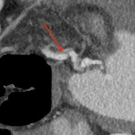

A 67-year-old man presented to the office for a general medical examination. He had no new or significant symptoms to report. Of particular interest, 16 years ago, abdominal ultrasonography for...